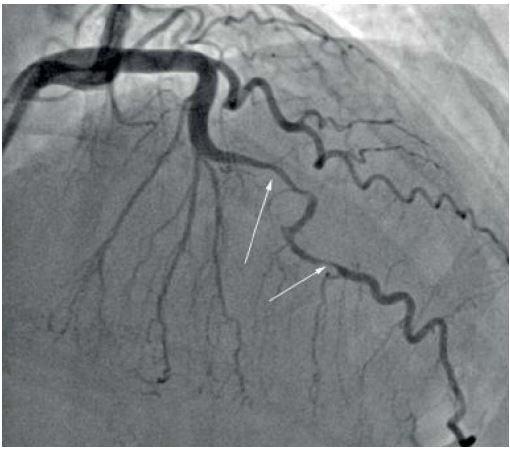

Mulher de 32 anos, deu entrada no em serviço de emergência com história de dor torácica. Conta que estava fazendo sua corrida rotineira de 5km quando apresentou forte dor precordial (intensidade 10/10) em aperto, de, associada a dispneia e sudorese, sem irradiação e que já durava mais de 1 hora. Previamente hígida, única medicação que fazia uso era anticoncepcional oral. Negava tabagismo ou história familiar de doenças cardíacas. Na chagada ao serviço de emergência foi realizado prontamente o ECG que é visto abaixo. O plantonista acionou a equipe de hemodinâmica, e a paciente foi levada ao cateterismo em 25 minutos. No momento do transporte sua dor melhorou (intensidade 2/10), e houve contato do laboratório dizendo que os marcadores de necrose miocárdica solicitados na urgência eram negativos. A imagem da coronariografia esquerda é apresentada abaixo. Baseado no caso clínico e imagem apresentada, qual opção melhor descreve o evento, e qual a melhor conduta?